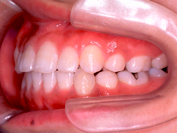

• 歯を抜くかどうかは、矯正治療をする上で非常に重要な問題です。そこで、治療方針を決める際にはまず検査をし、その検査結果を分析します。もちろん患者さんの希望も考慮にいれて、診断の際に最終的な判断をします。

• 歯を抜く場合には、どうして抜かないといけないのか、何本抜くのか、またどの歯を、いつ、どこの歯科医院で抜くのか(当クリニックでは、抜歯はゆきつけの歯科医院へお願いしています)などを分析資料を交えて説明致します。抜歯したスペースは、矯正治療によりどのように利用されますので、隙間が残ることはまずありません。抜く場合にはそれによりかみ合わせや、横顔等がどう変化するのかも、予測画像をお見せすることもできます。